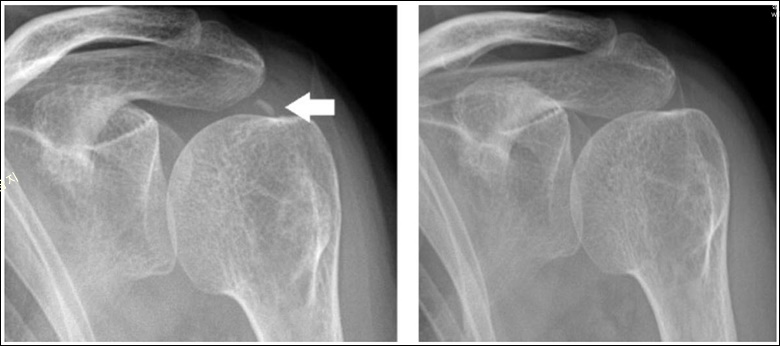

병원에서 어깨 석회화가 의심될 경우 엑스레이 촬영을 통해 확인이 가능하며, 형성 단계에 있는 미세한 크기의 석회는 초음파나 MRI 촬영을 통해 확인할 수 있습니다.